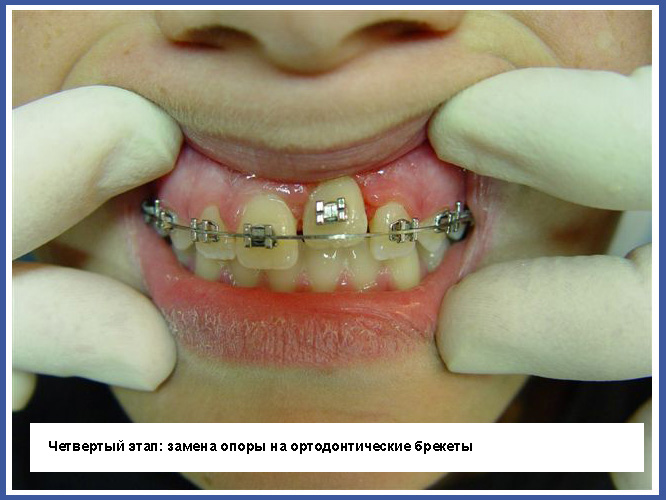

Ортодонтические брекеты (мост):

Это на сегодняшний день наиболее распространенное приспособление для выпрямления зубов. Брекеты приклеиваются к зубам, и проволочка, проходящая между ними, позволяет смещать зубы во всех трех измерениях при полном контроле над смещением, в отличие от пластинок, которые могут изменять только угол расположения зубов относительно челюсти. Брекеты могут быть как металлическими, так и прозрачными.

Брекеты, приклеиваемые к зубам, обладают многими преимуществами, но у них есть также и недостатки. Основной недостаток – это накопление остатков пищи и появление на нем микробов. Чтобы избежать опасности появления кариеса (дырок), нужно тщательнейшим образом чистить зубы в период лечения, и, насколько это возможно, избегать употребления пищи, ускоряющей развитие кариеса (пищи, богатой сахаром).